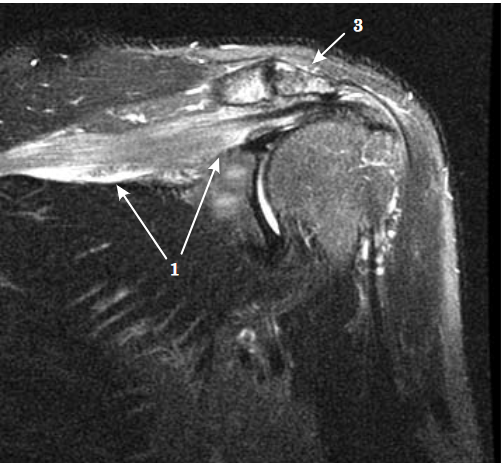

- Resonancia magnética: Cuando se sospeche de otra causa potencial (neoplasia, hernia cervical…) y nos puede mostrar si se realiza el estudio sobre la musculatura afectada. Mostrando patrones de edema difuso en fases iniciales y el aumento de infiltración grasa intramuscular en fase tardía.

Imágenes de este caso clínico